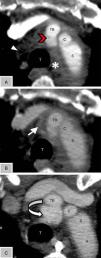

Traumatismo torácico: mínimo neumotórax bilateral. Angio-TC: se evidencia imagen sacular en el origen de la arteria innominada con morfología conservada en las distintas fases, compatible con seudoaneurisma postraumático; en fase venosa se evidencian focos de extravasación de contraste indicativos de focos de sangrado activo (ver figs. 1 y 2).

Figura 2.A: Angio-TC de tórax axial en fase arterial al ingreso, donde se observa imagen de adición sacular en el origen del tronco braquiocefálico (cabeza de flecha roja), con morfología conservada en las distintas fases, compatible con seudoaneurisma postraumático. Neumomediastino (cabeza de flecha blanca). B: Angio-TC de tórax axial en fase venosa, que presenta focos de extravasación de contraste (flecha blanca), indicativos de signos de sangrado activo. Zona de densidad de partes blandas periaórtica al cayado (*) compatible con hematoma aórtico. C: Angio-TC de tórax de control al mes del ingreso, donde se ha resuelto el hematoma periaórtico, con aumento del tamaño del seudoaneurisma (flecha curva): sin signos de sangrado activo.

A: arco aórtico; C: carótida izquierda; S: subclavia izquierda; T: tráquea; TB: tronco braquiocefálico (innominado).